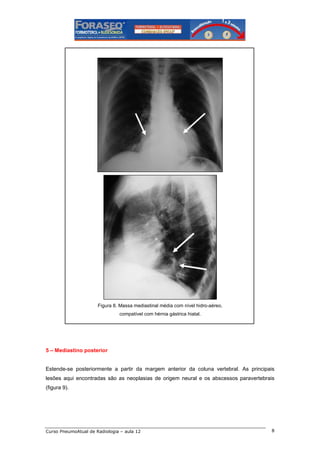

Figura 8. Massa mediastinal média com nível hidro-aéreo,

compatível com hérnia gástrica hiatal.